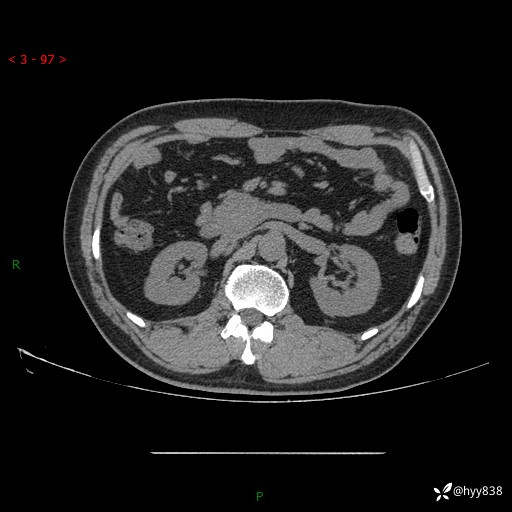

腹部CT平扫